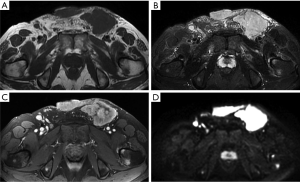

Desmoid-type fibromatosis

Desmoid-type fibromatosis is a relatively rare fibroblastic proliferative disease, previously referred to as aggressive fibromatosis or desmoid tumors. These tumors do not metastasize, but relapse can easily occur after surgical treatment. In some studies, desmoid-type fibromatosis has been described as the most common soft tissue tumor in the abdominal wall (1,24); however, this may be because lipomas are not usually treated surgically and were excluded from the analysis. Typically, these tumors occur in young females aged 20 to 40 years, more frequently during the first year after childbirth (25). Arising from the aponeurosis of the abdominal wall muscle, desmoid fibromatosis usually occurs in the anterior abdominal wall and is usually located in the rectus abdominis, the internal oblique muscles, and the surrounding fascia. Due to the distinct location and tendency of these lesions to develop in women of childbearing age, they can usually be distinguished from other forms of deep desmoid-type fibromatosis.

On CT, desmoid-type fibromatosis usually appears as a round or oval, nonspecific soft tissue mass with a density similar to that of muscle. Generally, it does not grow across the midline and is significantly enhanced after contrast injection. It shows low-to-intermediate signal intensity (SI) on T1WI and high SI on T2WI. Internal band-like findings of low signal heterogeneity on all sequences are relatively distinct on MRI (Figure 4). These low-SI bands are common (62–91% of cases) in desmoid-type fibromatosis compared with other neoplastic lesions and are related to the collagenized and hypocellular band regions observed on gross pathological examination, representing fibrous and collagenized regions (26,27). Extension along fascial planes (i.e., the “fascial tail” sign) adds specificity for the diagnosis (Figure 3) (24,28). MRI is optimal for detecting deep intra-abdominal extension that, although unusual, is important for guiding complete surgical resection. High SI on T2WI has been shown to correlate with greater cellularity and an increased recurrence rate (29).